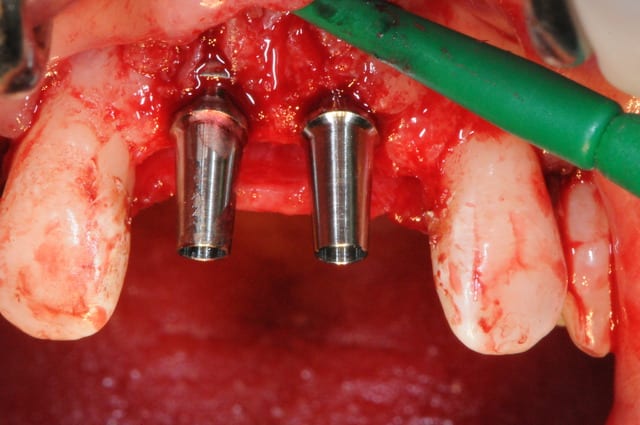

juste pour le plaisir des yeux...

j'étais hier à Strasbourg dans une formation avec Fouad Khoury.

génial ce type!

oui biobank et granules de biobank par dessus.

Et avec de l'autogène, Fouad sera certainement plus content! Et sans PRF, aussi ;-)

effectivement, avec de l'autogène, je pense que ce sera peut être mieux.

oui mais avec le biobank : pas de 2éme site, temps opé réduit, moins de stress, moins de suite douloureuse.

Inconvénient : ce n'est pas de l'autogène...mais est-ce réellement un problème ? !

Je trouve que tu ne gagnes rien en épaisseur au niveau de la crête ( mais on ne vois pas bien avec le lambeau , tu as peut être assez ? ).

Pour juste combler les dépressions, tes deux vis en piquets de tente sans bloc auraient fait aussi bien.

Sans membrane collagène sous le PRF , tu ne crains pas de perdre tous tes granules ?

Si tu prélèves en retromolaire, dans ce cas, je verrais bien un box pour épaissir aussi la crête .

Ou alors avec une membrane en PDLLA .